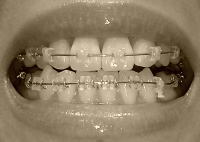

以下、画像です。

060905f.jpg 7月14日

061113a.jpg 今日

060905b.jpg 6月20日

061129c.jpg 今日

060913a.jpg 7月14日